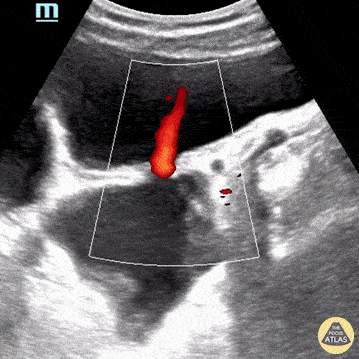

A middle aged male presented with lower abdominal pain and difficulty urinating. He also reported incomplete bladder emptying. POCUS demonstrated multiple bladder diverticuli that were subsequently confirmed on CT pelvis. Acquired bladder diverticula are often secondary to bladder outlet obstruction that may be related to an enlarged prostate, urethral stricture, or neurologic disease. Lydia Mansour, DO, PGY1 & Sohaib Mandoorah, MD, PGY3 Central Michigan University Emergency Medicine Residents